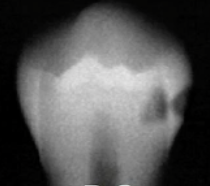

rarefying osteitis

what type of lesion is shown here

widened PDL, moderately well defined periapical radiolucency

radiographic features of rarefying osteitis